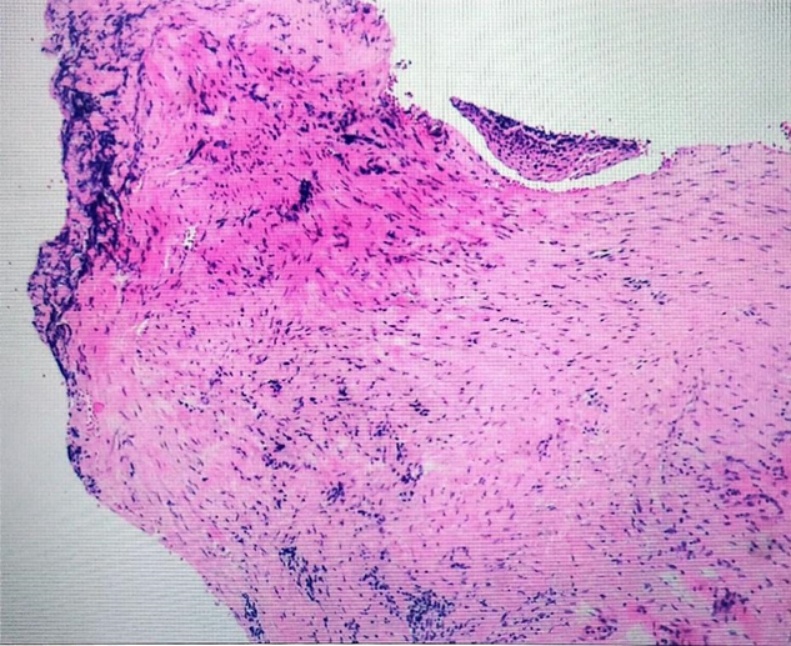

入院后完善血常规、血生化、凝血四项、术前九项、尿便常规、心电图、胸片等检查,电子喉镜下检查(见图1)会厌喉面双侧室带前中部可见一粉红色新生物。排除手术禁忌症后,2024年10月11日全麻前联合镜下喉功能重建术 + 喉噗黏连松解术,手术经过:1. 患者取仰卧位,气管插管静脉麻醉后常规消毒、铺巾;2. 经口导入前联合镜,见室带前中处与会厌喉面有1 × 1.5 cm大小粉红色新生物,局部白色瘢痕样组织增生,与周围组织分界清楚,表面平整,未见破溃、糜烂、出血及异常分泌物,术中切除新生物松解粘连室带,喉剪修剪新生物边缘,电凝新生物基底止血,检查无组织残留,取新生物病损送病检;4. 术毕,安返,术中出血约5 ml。术后激素抗炎、消肿,止血,雾化吸入对症治疗。术后病理检查(图2)示:(喉部病损)送检组织衬覆少许鳞状上皮,固有层充血、出血及水肿,伴梭形细胞及胶原纤维增生,淋巴细胞、浆细胞和少许中性粒细胞浸润,考虑瘤样纤维组织增生。免疫组化结果回报:SOX-10 (−),β-catenin (−),SMA (+),Ki67 (个别细胞+),MSA (−),Desmin (−),CD34 (血管+),MyoD1 (−),myogenin (−),STAT6 (−),Vimentin (+),ALK (−)。特殊染色结果:弹力纤维(−)。术后予以消肿、禁声、止血等对症治疗,术后我们进行了随访,在随访复查中,患者恢复良好,术后复查电子喉镜(图3)示:喉蹼术后改变,声带活动好,闭合可。患者声嘶改善,呼吸较术前顺畅,无咽痛、咽痒、吞咽困难、咳痰、痰中带血等不适,康复出院。

Figure 2. Shows the pathological results of the patient’s laryngeal lesion: under the microscope, lymphocytes, plasma cells, and a few neutrophils are observed infiltrating the tissue

2. 为患者喉部病损病理结果:镜下见淋巴细胞、浆细胞和少许中性粒细胞浸润